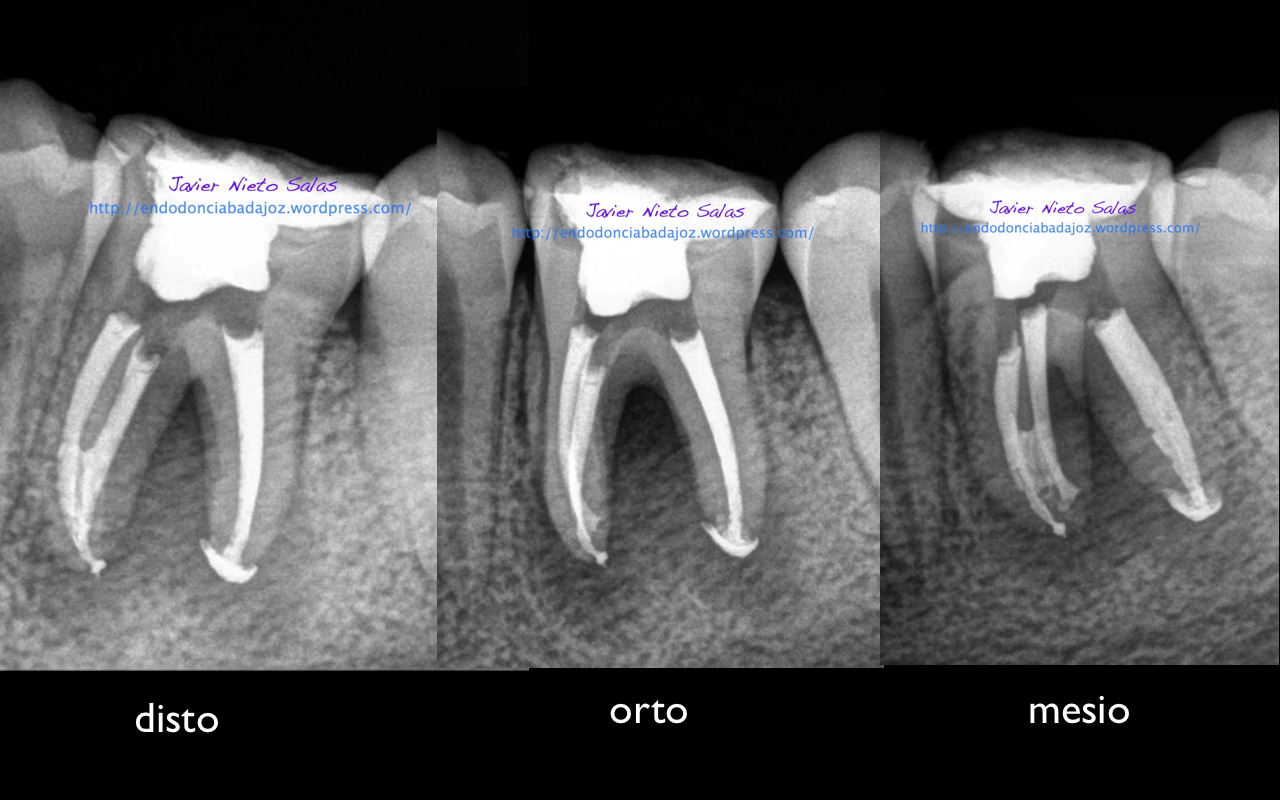

Se trata de un par de molares inferiores con lesiones apicales (Periodontitis apicales crónicas ). Consecuencia de caries profundas en su momento.

Se tratan del caso A y el caso B, por orden de posición, ambos casos se instrumentaron de la misma manera, elegimos Protaper hasta una F2, ambos casos se realizaron en una sesión tras abundante irrigación y finalmente se obturaron con condensación Vertical con la técnica de Ola continua de Buchanan complementando en el backfilling con guatpercha inyectada con la Pistola Obtura II.

Caso A:

Llamamos a la paciente a revisión a los 10 meses: